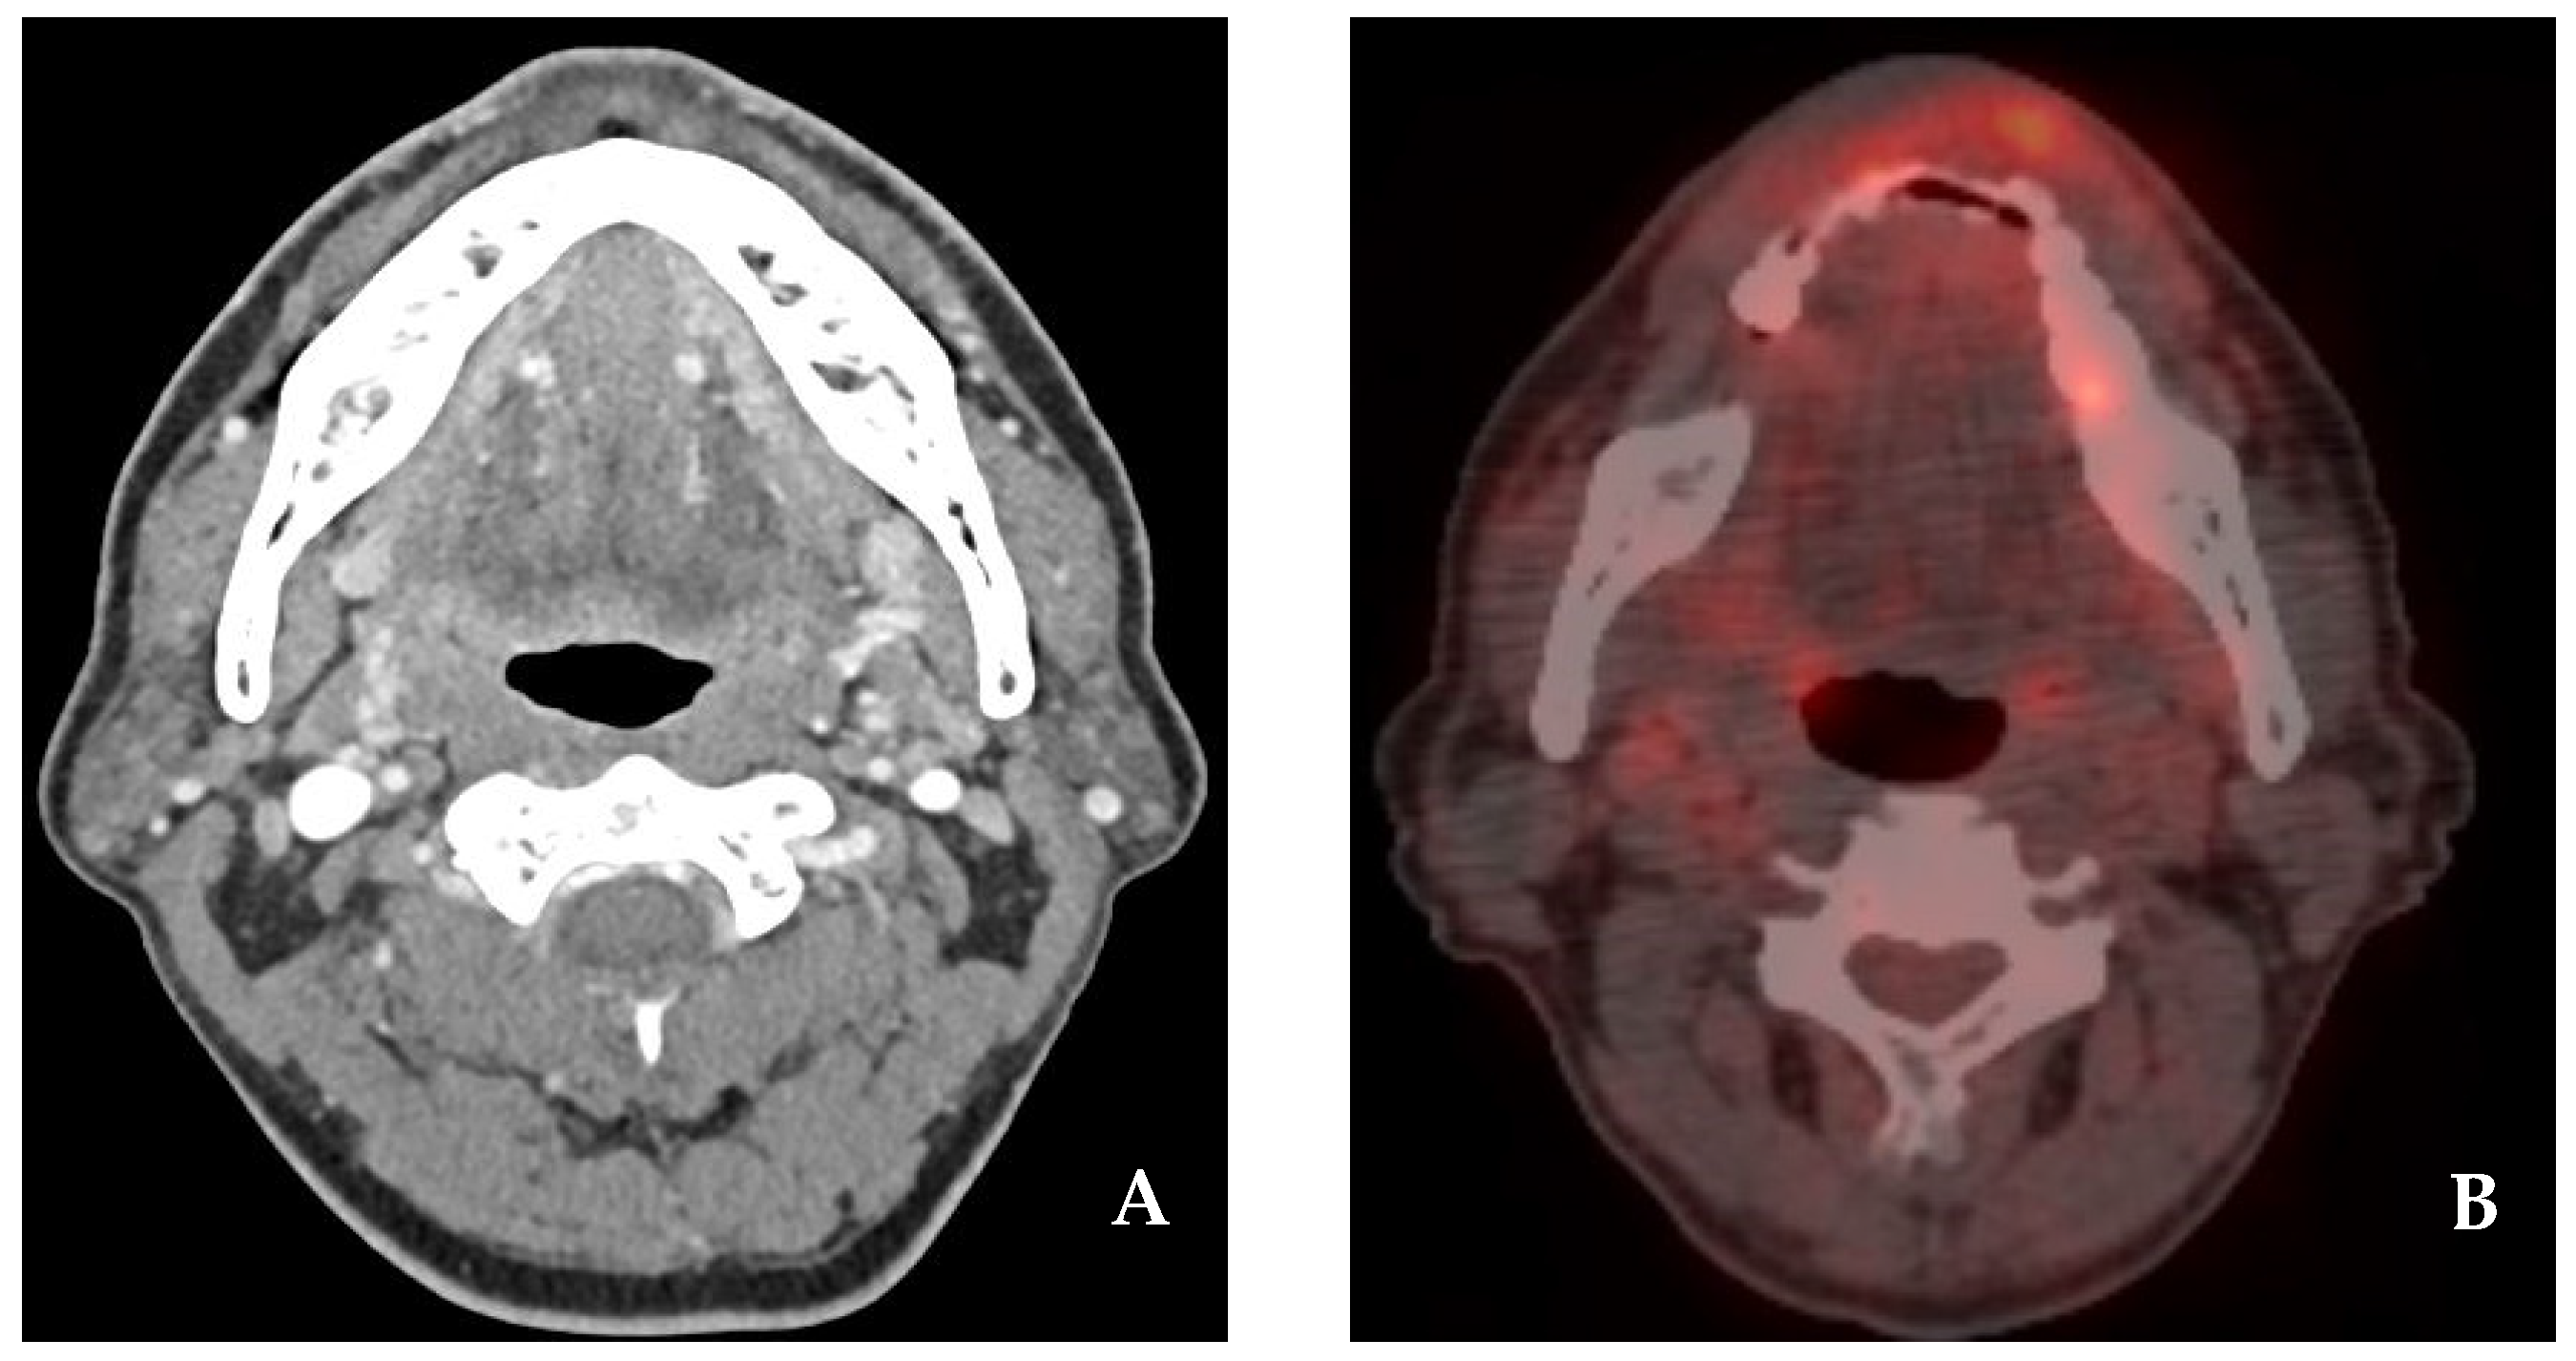

2.1. Case 1